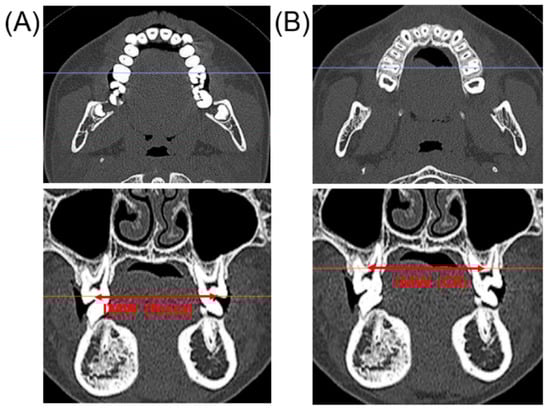

2.2. Skeletal and Dental Evaluation